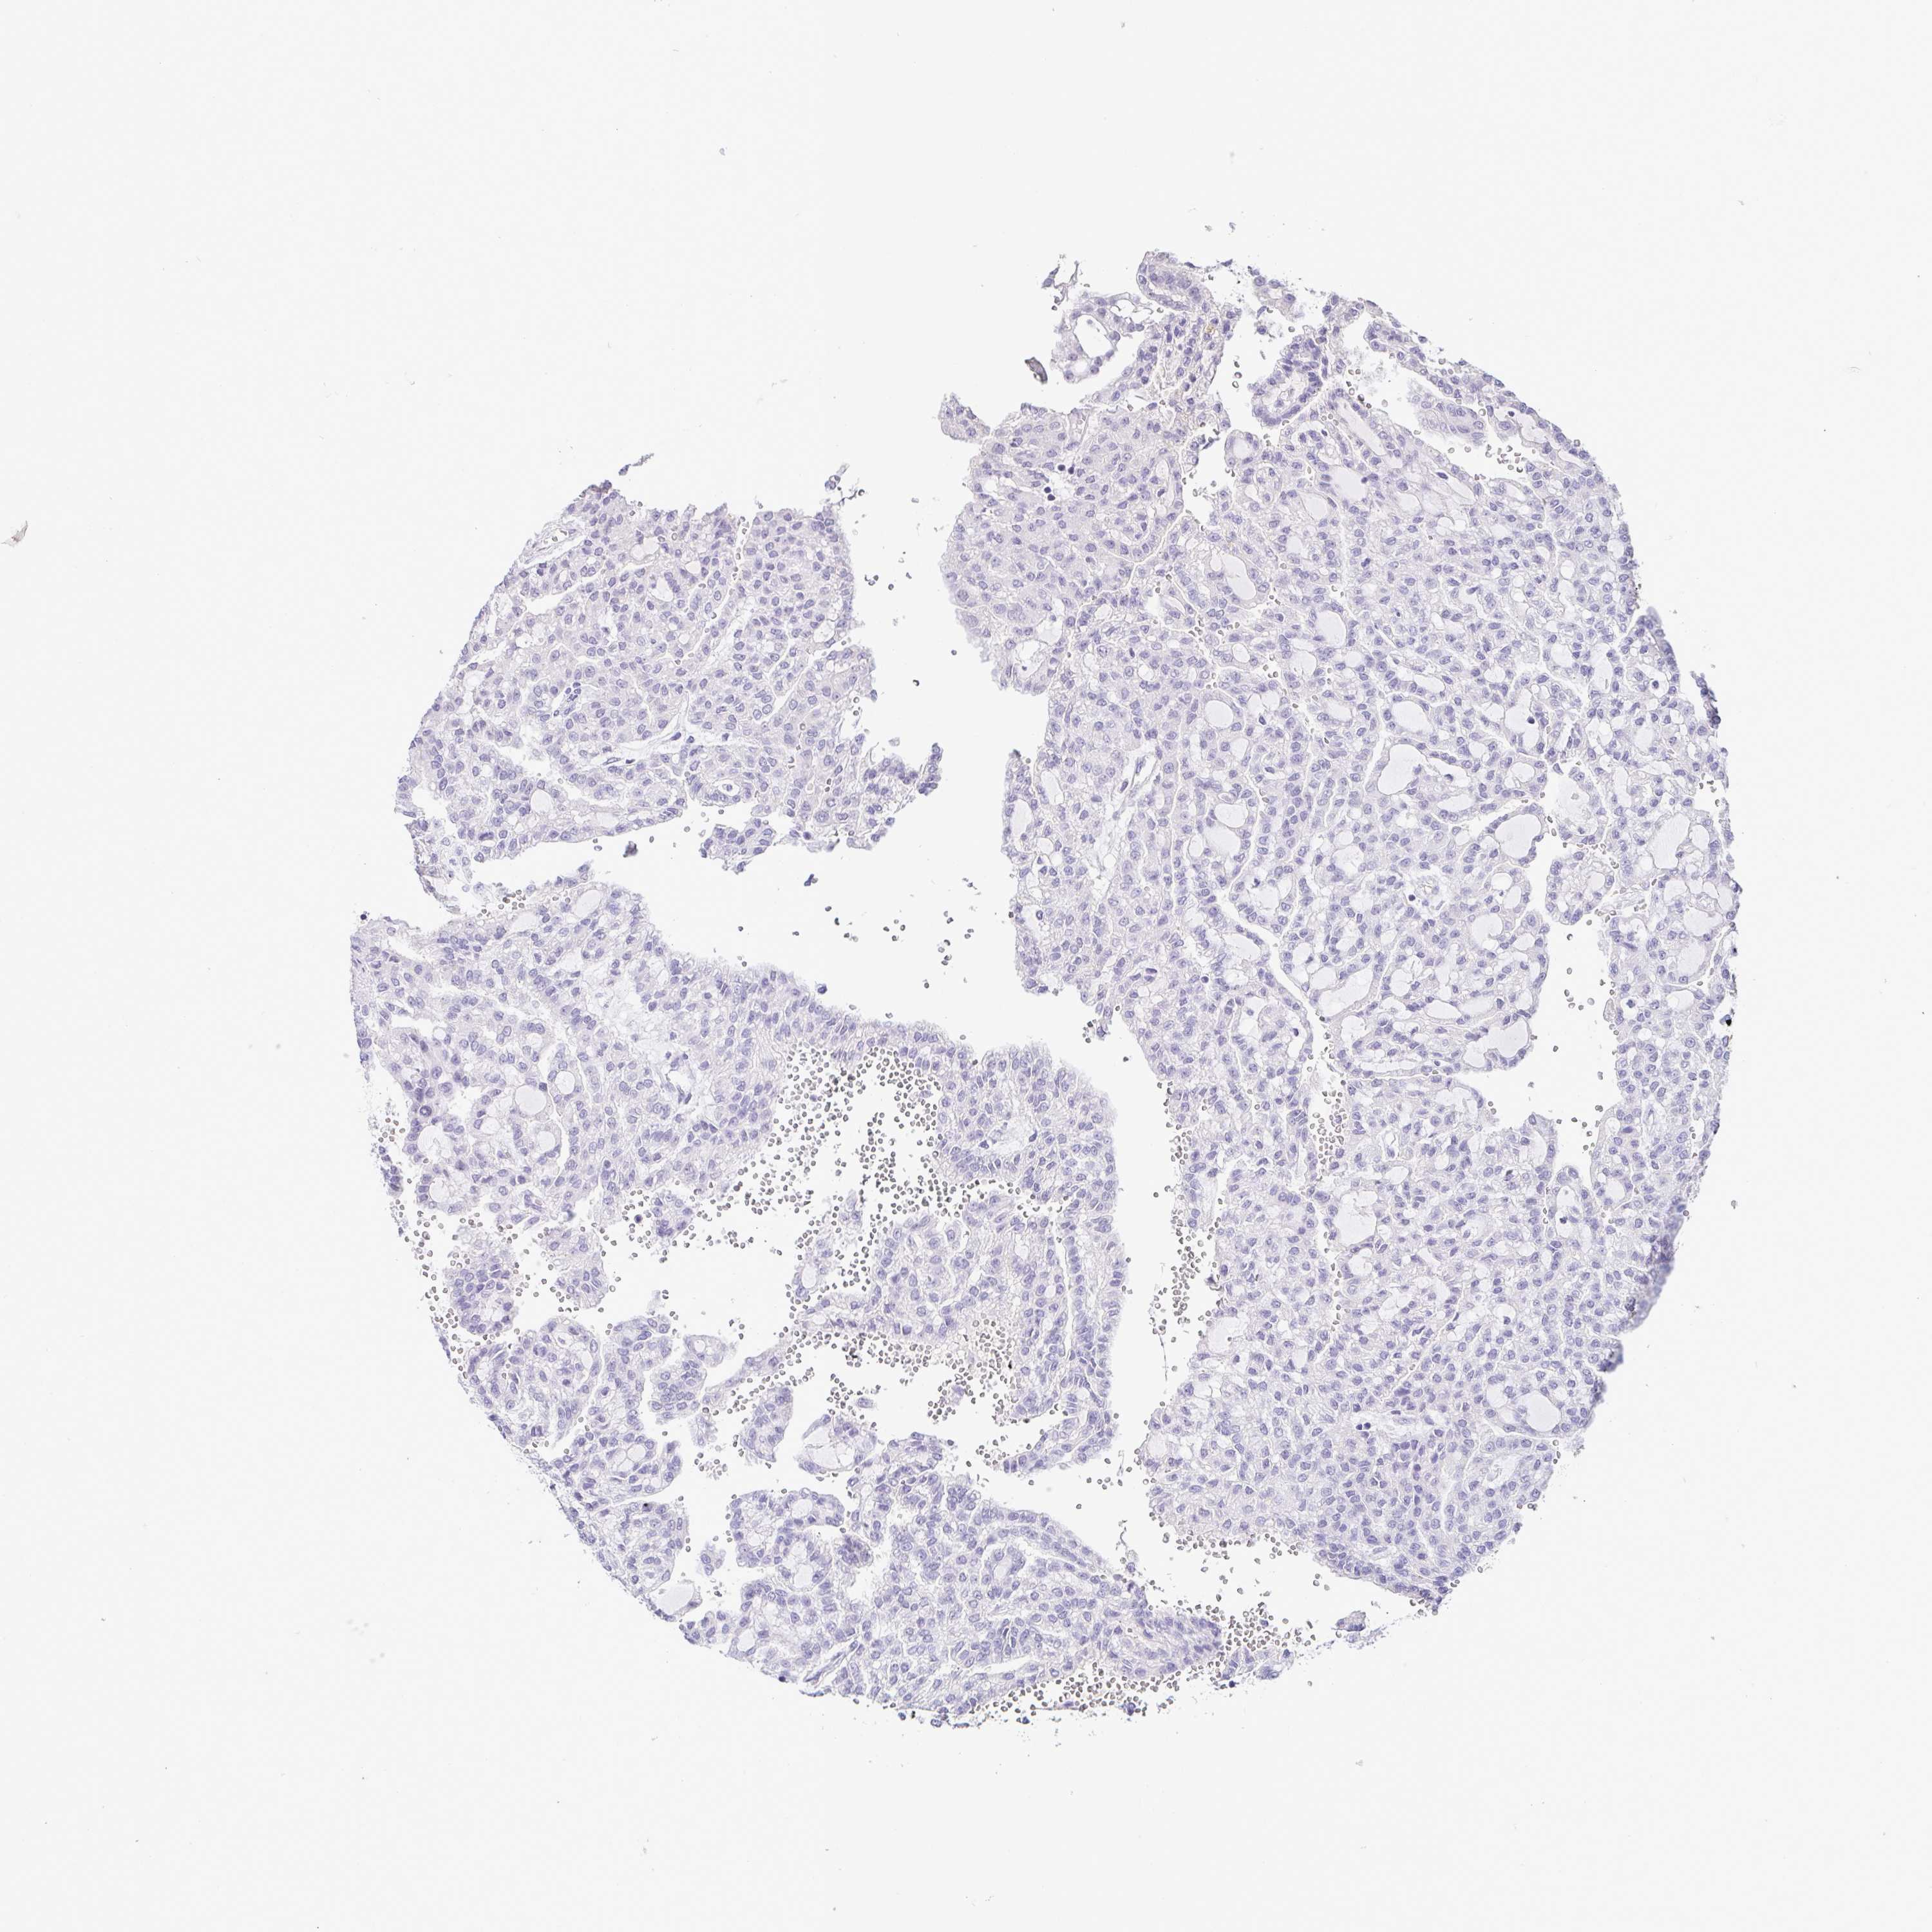

KIDNEY RENAL PAPILLARY CELL CARCINOMA (TCGA) - Interactive survival scatter ploti

The Survival Scatter plot shows the clinical status (i.e. dead or alive) for all individuals in the patient cohort, based on the same data that underlies the corresponding Kaplan-Meier plots. Patients that are alive at last time for follow-up are shown in blue and patients who have died during the study are shown in red.

The x-axis shows the expression levels (FPKM) of the investigated gene in the tumor tissue at the time of diagnosis. The y-axis shows the follow-up time after diagnosis (years). Both axes are complimented with kernel density curves demonstrating the data density over the axes. The top density plot shows the expression levels (FPKM) distribution among dead (red) and alive patients (blue). The right density plot shows the data density of the survived years of dead patients with high and low expression levels respectively, stratified using the cutoff indicated by the vertical dashed line through the Survival Scatter plot. This cutoff is automatically defined based on the FPKM cutoff that minimizes the p-score. The cutoff can be changed by dragging the vertical line or by entering a cutoff value in the square labeled "Current cut-off".

Under the Survival Scatter plot the p-score landscape (black curve; left axis) is shown together with dead median separation (red curve; right axis). Dead median separation is the difference in median mRNA expression between patients who have died with high and low expression, respectively. It is calculated as follows: median FPKM expression of dead patients with high expression - median FPKM expression of dead patients with low expression. This is intended to aid the user in visually exploring custom cutoffs and the associated p-scores and dead median separation.

Individual patient data is displayed and can be filtered by clicking on one or more of the category buttons on the top of the page. Categories describing expression level and patient information include: high, low, alive, dead, female, male and tumor stages. The scale of the x-axis can be toggled between linear and log-scale by clicking on the "x log" button. Mouse-over function shows TCGA ID, patient information and mRNA expression (FPKM) for each patient.

& Survival analysisi

Kaplan-Meier plots summarize results from analysis of correlation between mRNA expression level and patient survival. Patients were divided based on level of expression into one of the two groups "low" (under cut off) or "high" (over cut off). X-axis shows time for survival (years) and y-axis shows the probability of survival, where 1.0 corresponds to 100 percent.

TCF3 is not prognostic in Kidney Renal Papillary Cell Carcinoma (TCGA)